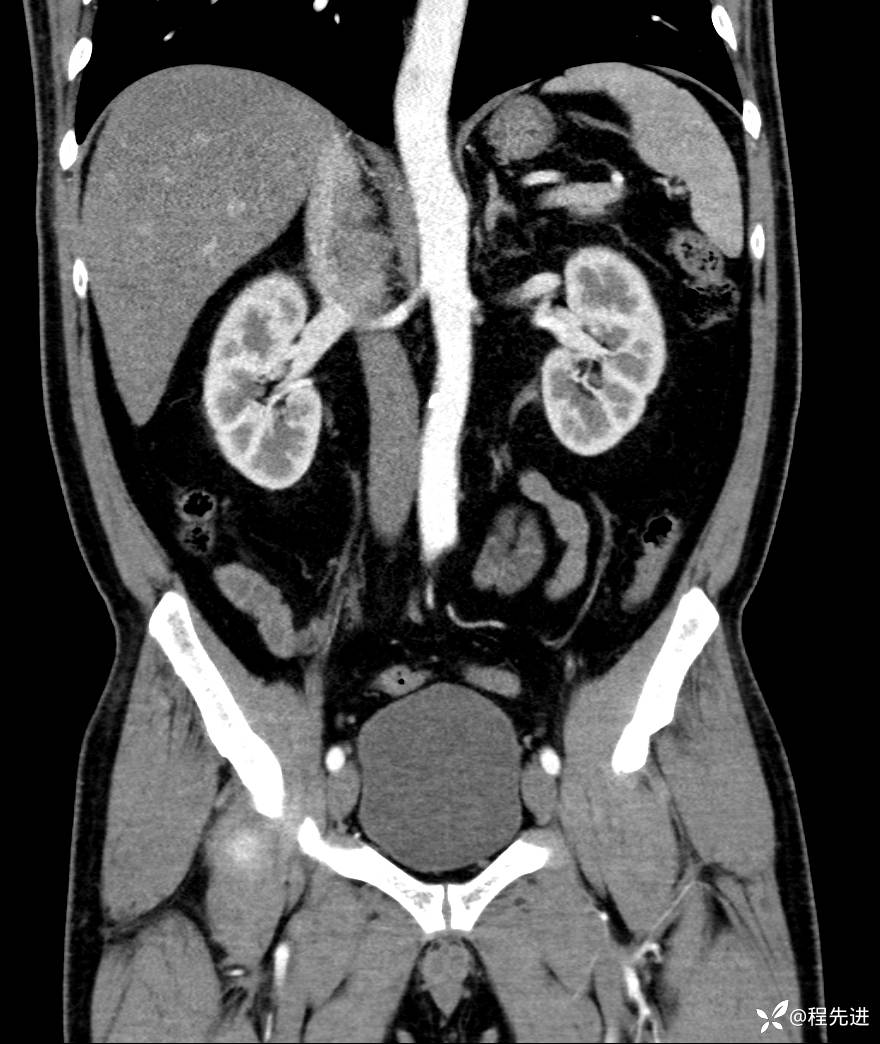

【腹盆】特别精彩病例|发现腹膜后肿物1月余

主诉:发现腹膜后肿物1月余

现病史:患者1月余前查体,行超声检查提示:后腹膜囊实性肿块;慢性胆囊炎伴胆囊内结石;无腹痛腹胀,不伴腹泻发热等;偶感腰背部酸痛。

CT平扫+增强: